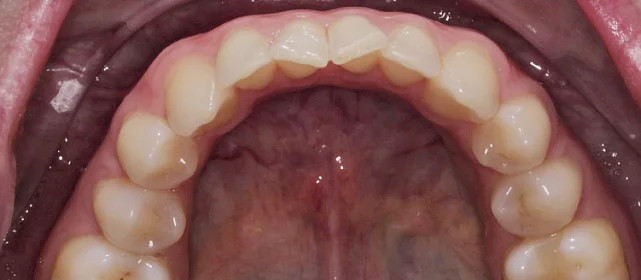

Скученность зубов, обе челюсти сужены — зубам не хватало места в ряду.

Проблема: Пациентка обратилась с одной жалобой — неровные зубы. При осмотре обнаружили, что обе челюсти сужены, зубам банально не хватает места, отсюда скученность. Зубы здоровые, ортопедия не нужна — чисто ортодонтический случай.